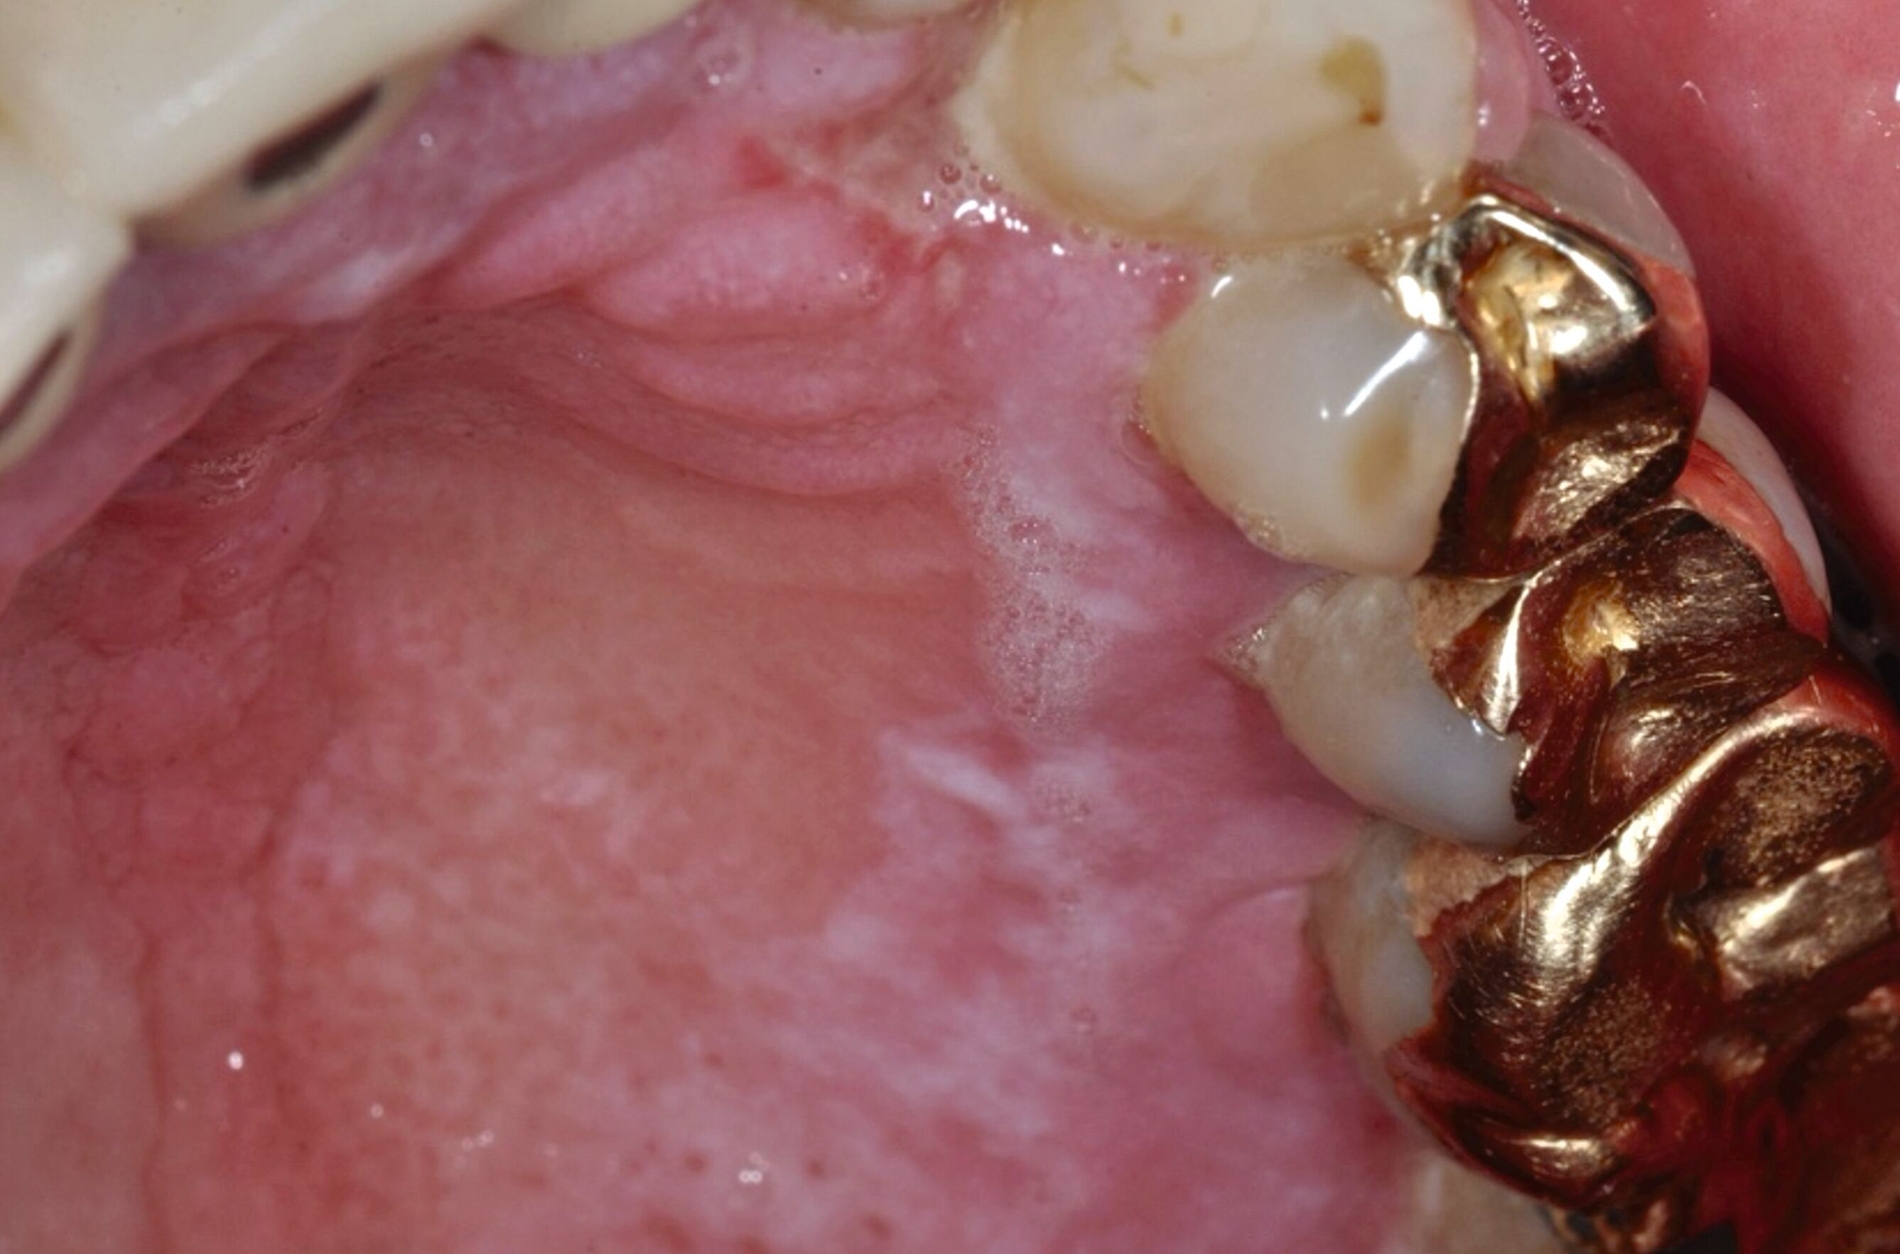

Ein 70-jähriger Patient mit langjährigem, erosivem OLP zeigte deutliche Anzeichen einer malignen Transformation. Eine Inzisionsbiopsie nach einem Tumorstaging weist ein orales Plattenepithelkarzinom (cT4a, cN0, cM0) nach (Abbildungen 10 und 11). Im Anschluss fand die erforderliche chirurgische Therapie statt, in deren Folge eine Hemimaxillektomie und eine Rekonstruktion mit einem mikrovaskulär anastomosierten Fibulatransplantat notwendig wurden. Der Tumor mit einem Durchmesser von 3,5 cm, der den Knochen infiltrierte, konnte vollständig entfernt werden. Der Patient befindet sich fünf Jahre nach der Resektion in der klinischen Nachsorge und leidet periodisch unter weiteren Schüben seines OLP.